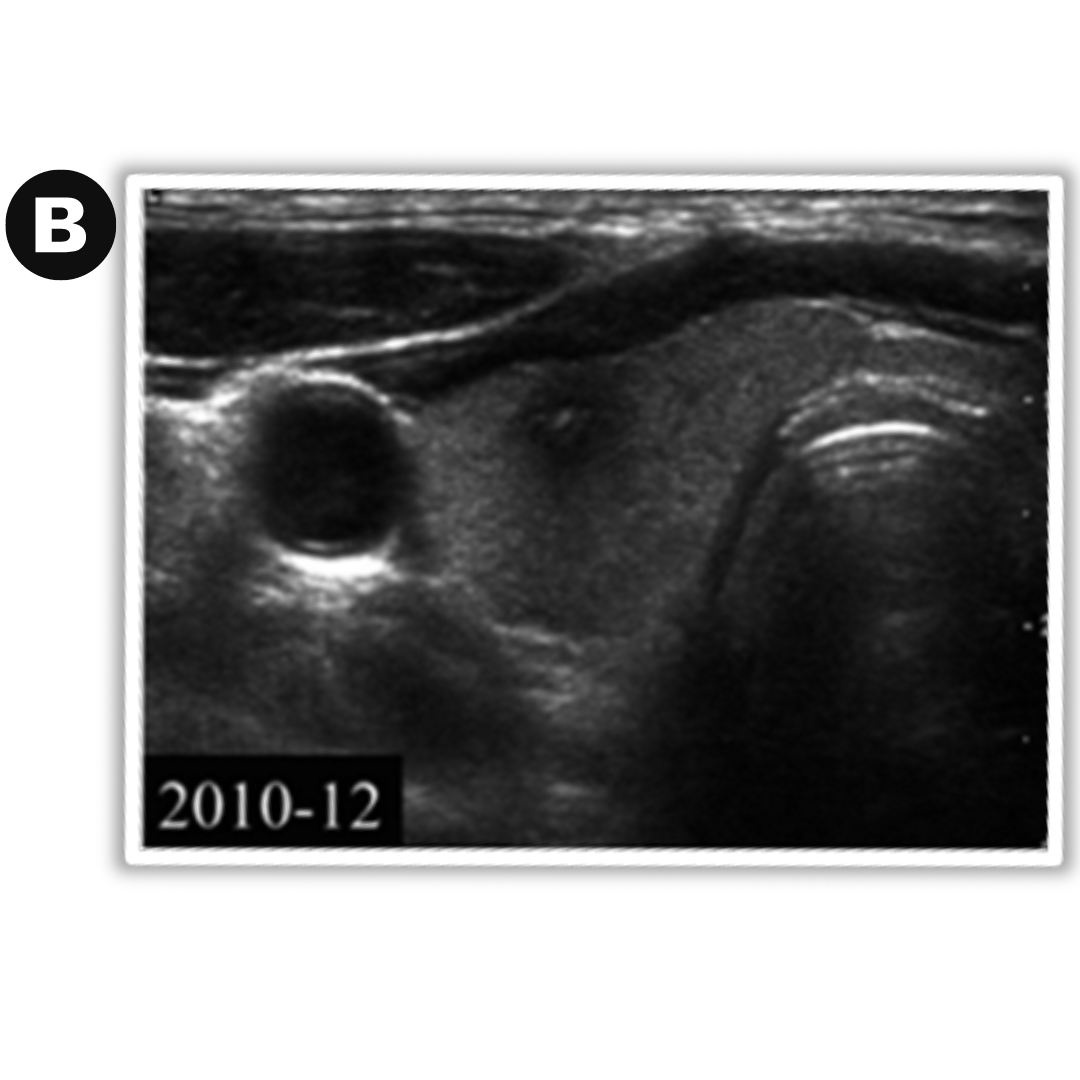

Caso 01: Nódulo en control a) diciembre 2007 nódulo coloideo predominantemente quístico b) diciembre 2010 nódulo en degeneración, muestra un nódulo sólido hipoecoico con focos ecogénicos.